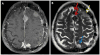

This article provides an overview of the neuroimaging literature focused on preoperative prediction of meningioma consistency. A validated, noninvasive neuroimaging method to predict tumor consistency can provide valuable information regarding neurosurgical planning and patient counseling. Most of the neuroimaging literature indicates conventional MRI using T2-weighted imaging may be helpful to predict meningioma consistency; however, further rigorous validation is necessary. Much less is known about advanced MRI techniques, such as diffusion MRI, MR elastography (MRE), and MR spectroscopy. Of these methods, MRE and diffusion tensor imaging appear particularly promising.